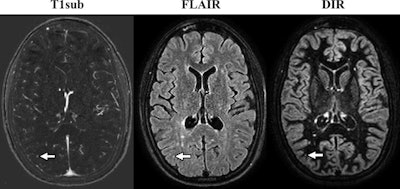

Axial MR images come from a 32-year-old woman with relapsing-remitting multiple sclerosis. Images were obtained with the subtraction of an unenhanced T1-weighted MR image from contrast-enhanced MR image (T1sub), FLAIR, and DIR. A new small subcortical lesion (arrow) in the right parietal lobe is seen only on the contrast-enhanced image but is overlooked on DIR and FLAIR sequences. There are several other new or enlarged lesions that can be seen on nonenhanced images. Images courtesy of Radiology.

Axial MR images come from a 32-year-old woman with relapsing-remitting multiple sclerosis. Images were obtained with the subtraction of an unenhanced T1-weighted MR image from contrast-enhanced MR image (T1sub), FLAIR, and DIR. A new small subcortical lesion (arrow) in the right parietal lobe is seen only on the contrast-enhanced image but is overlooked on DIR and FLAIR sequences. There are several other new or enlarged lesions that can be seen on nonenhanced images. Images courtesy of Radiology."In our cohort, contrast-enhanced T1-weighted MRI provided no benefit at a per-patient level over longitudinal subtraction maps obtained from nonenhanced sequences for detecting new or enlarged lesions in 507 follow-up examinations of patients with MS," Eichinger and colleagues concluded. "In no case was interval progression missed when only nonenhanced sequences were analyzed. On a per-lesion basis, less than 1% of new or enlarged lesions were overlooked when only nonenhanced sequences were analyzed."